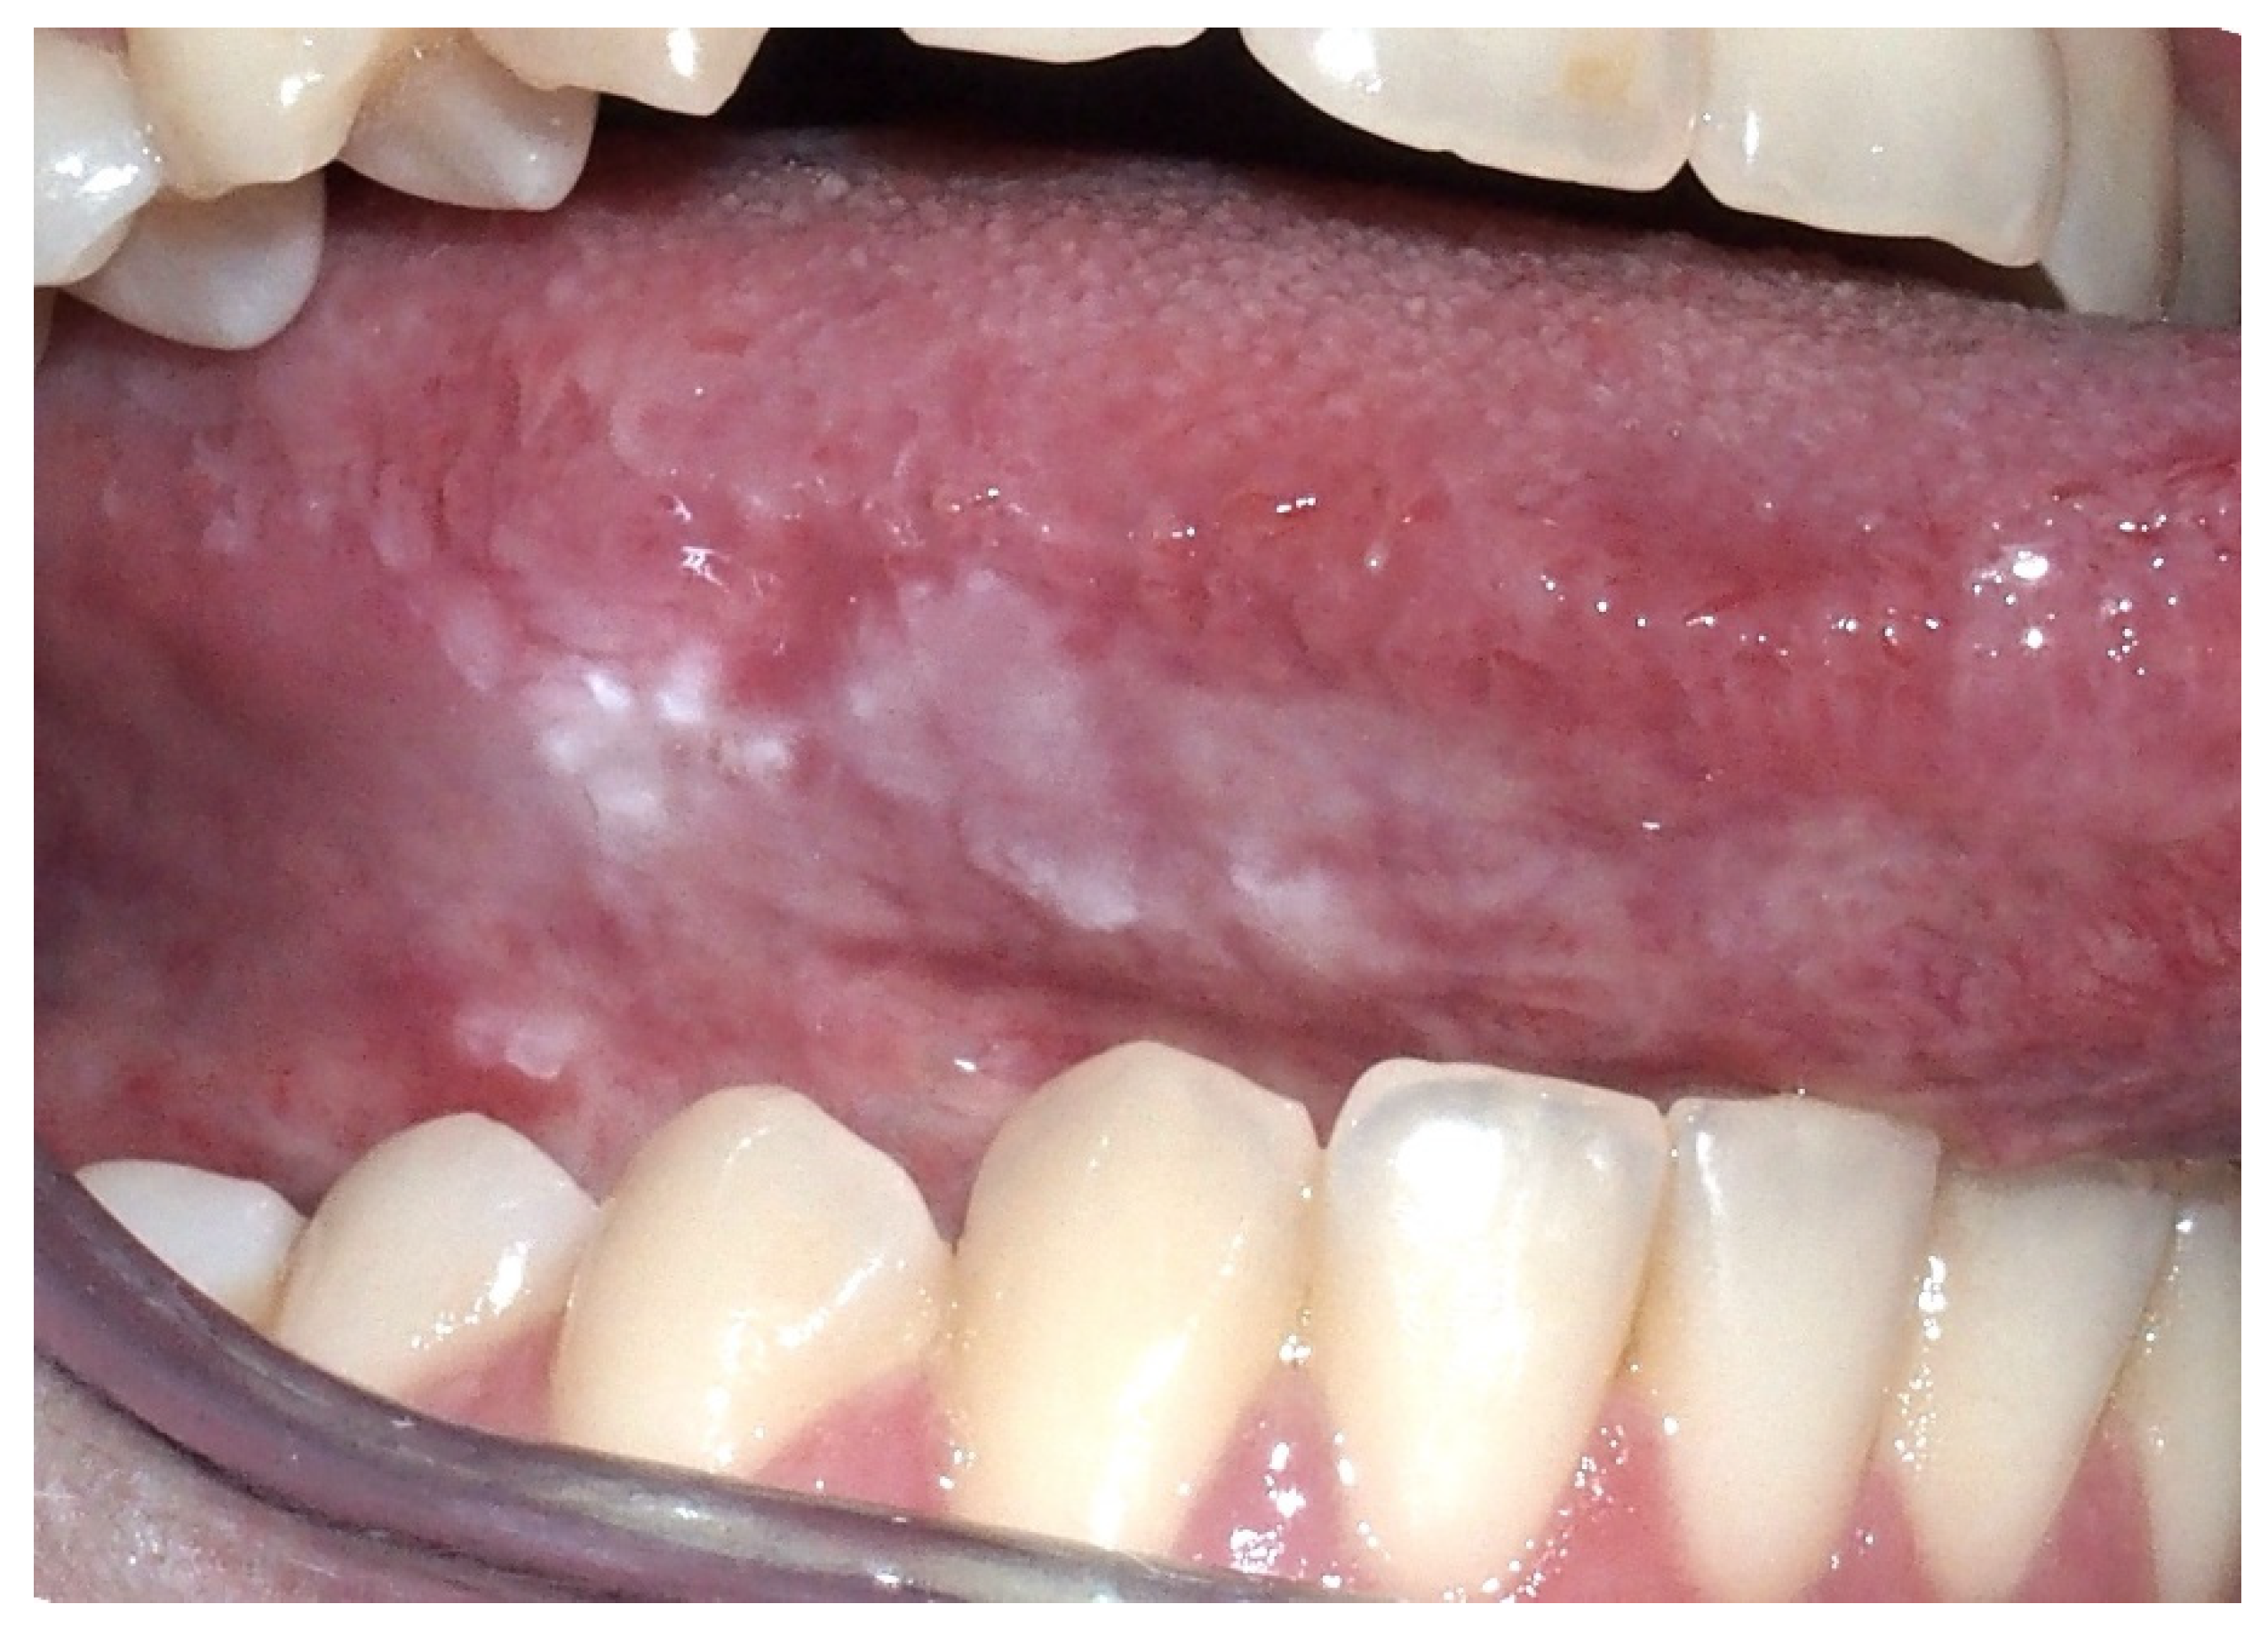

2.3. Oral Lichen Planus